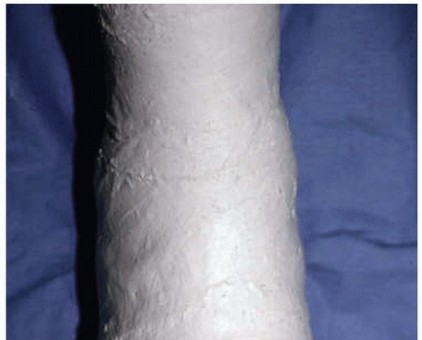

Immobilization with a boot or cast. A toe spica cast with the hallux in plantarflexion relieves tension on the injured plantar complex (FIG 6). Found to be very helpful with a diastased bipartite or fractured sesamoid.

FIG 6 • Plaster toe spica cast for conservative or postoperative care of a turf toe injury.